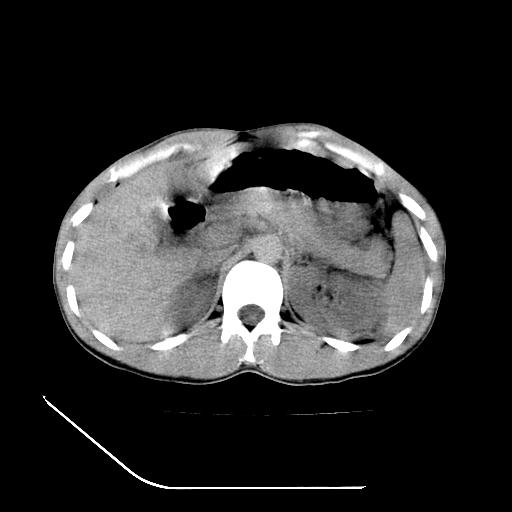

m-25y 高空堕落 12 月5号

12月7号病人尿量200ml/24h 急查双肾ct

左肾挫裂伤并肾周血肿;

肝肾间隙可见液区,建议手术探查;

支持:1、左肾挫裂伤并肾周血肿;

2、少量腹水;

3、左肾旋转不良;

4、反射性肠淤张。

除了1:左肾挫裂伤并肾周血肿;

2:少量腹水

第二次ct检查后:临床医生腹水穿刺后考虑肠系膜动脉破裂,后实行剖腹探查:于空肠距离十二指肠90cm处发现肠管破裂,破裂口较小;修补后关腹。

顺便请各位老师认真看看7号片

各位老师觉得胆囊是不是有点积血。我在原始片看胆囊密度不均,似有小液平面

再有就是支持楼主,胆囊7日片比5日片不仅增大许多,靠后下更见液液分层,应该是有积血。